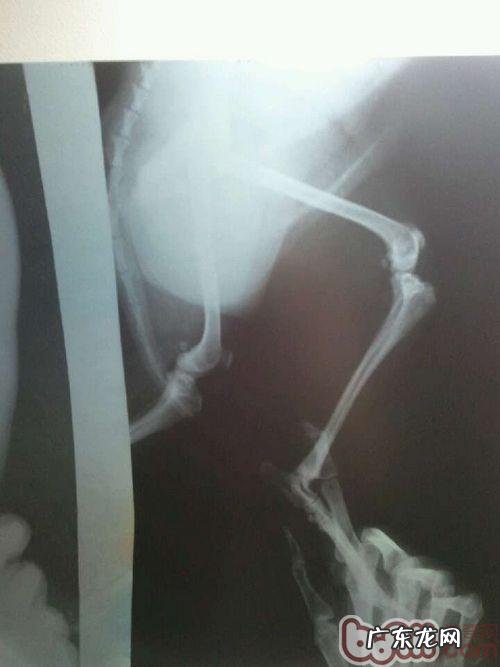

文章插图

髌骨脱位逆位X光图